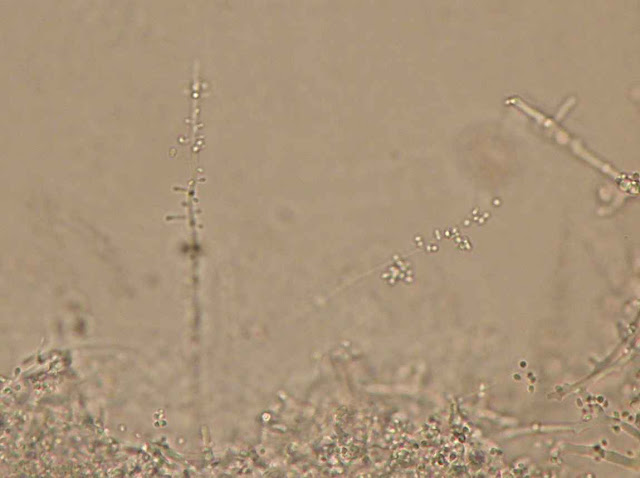

O exame microscópico confirma a identificação de T. mentagrophytes: hifas em espiral, microconideos esféricos.

Hifa em espiral.

Hifa e microconideos.

Hifa com microconideos agrupados.